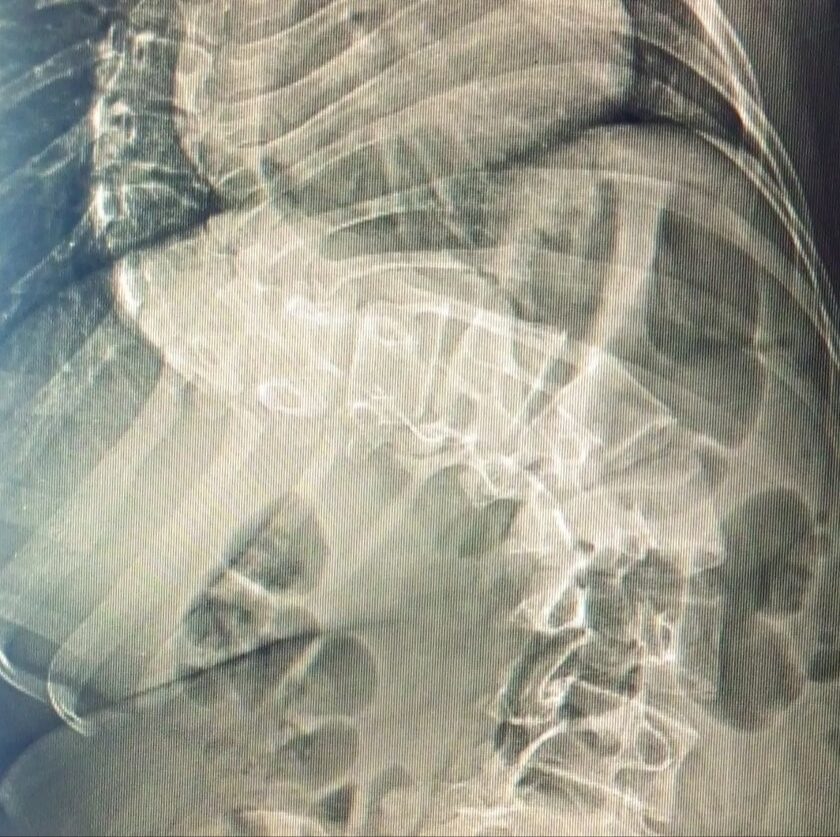

Jesús Urquiola, tío de la joven, expresó que María Valentina fue diagnosticada con escoliosis idiopática de la adolescencia, de alto grado, con una curvatura de 112 por ciento que le impide llevar una vida normal.

La adolescente sufre de escoliosis idiopática de la adolescencia de alto grado, con una curvatura de 112 por ciento que le impide llevar una vida normal